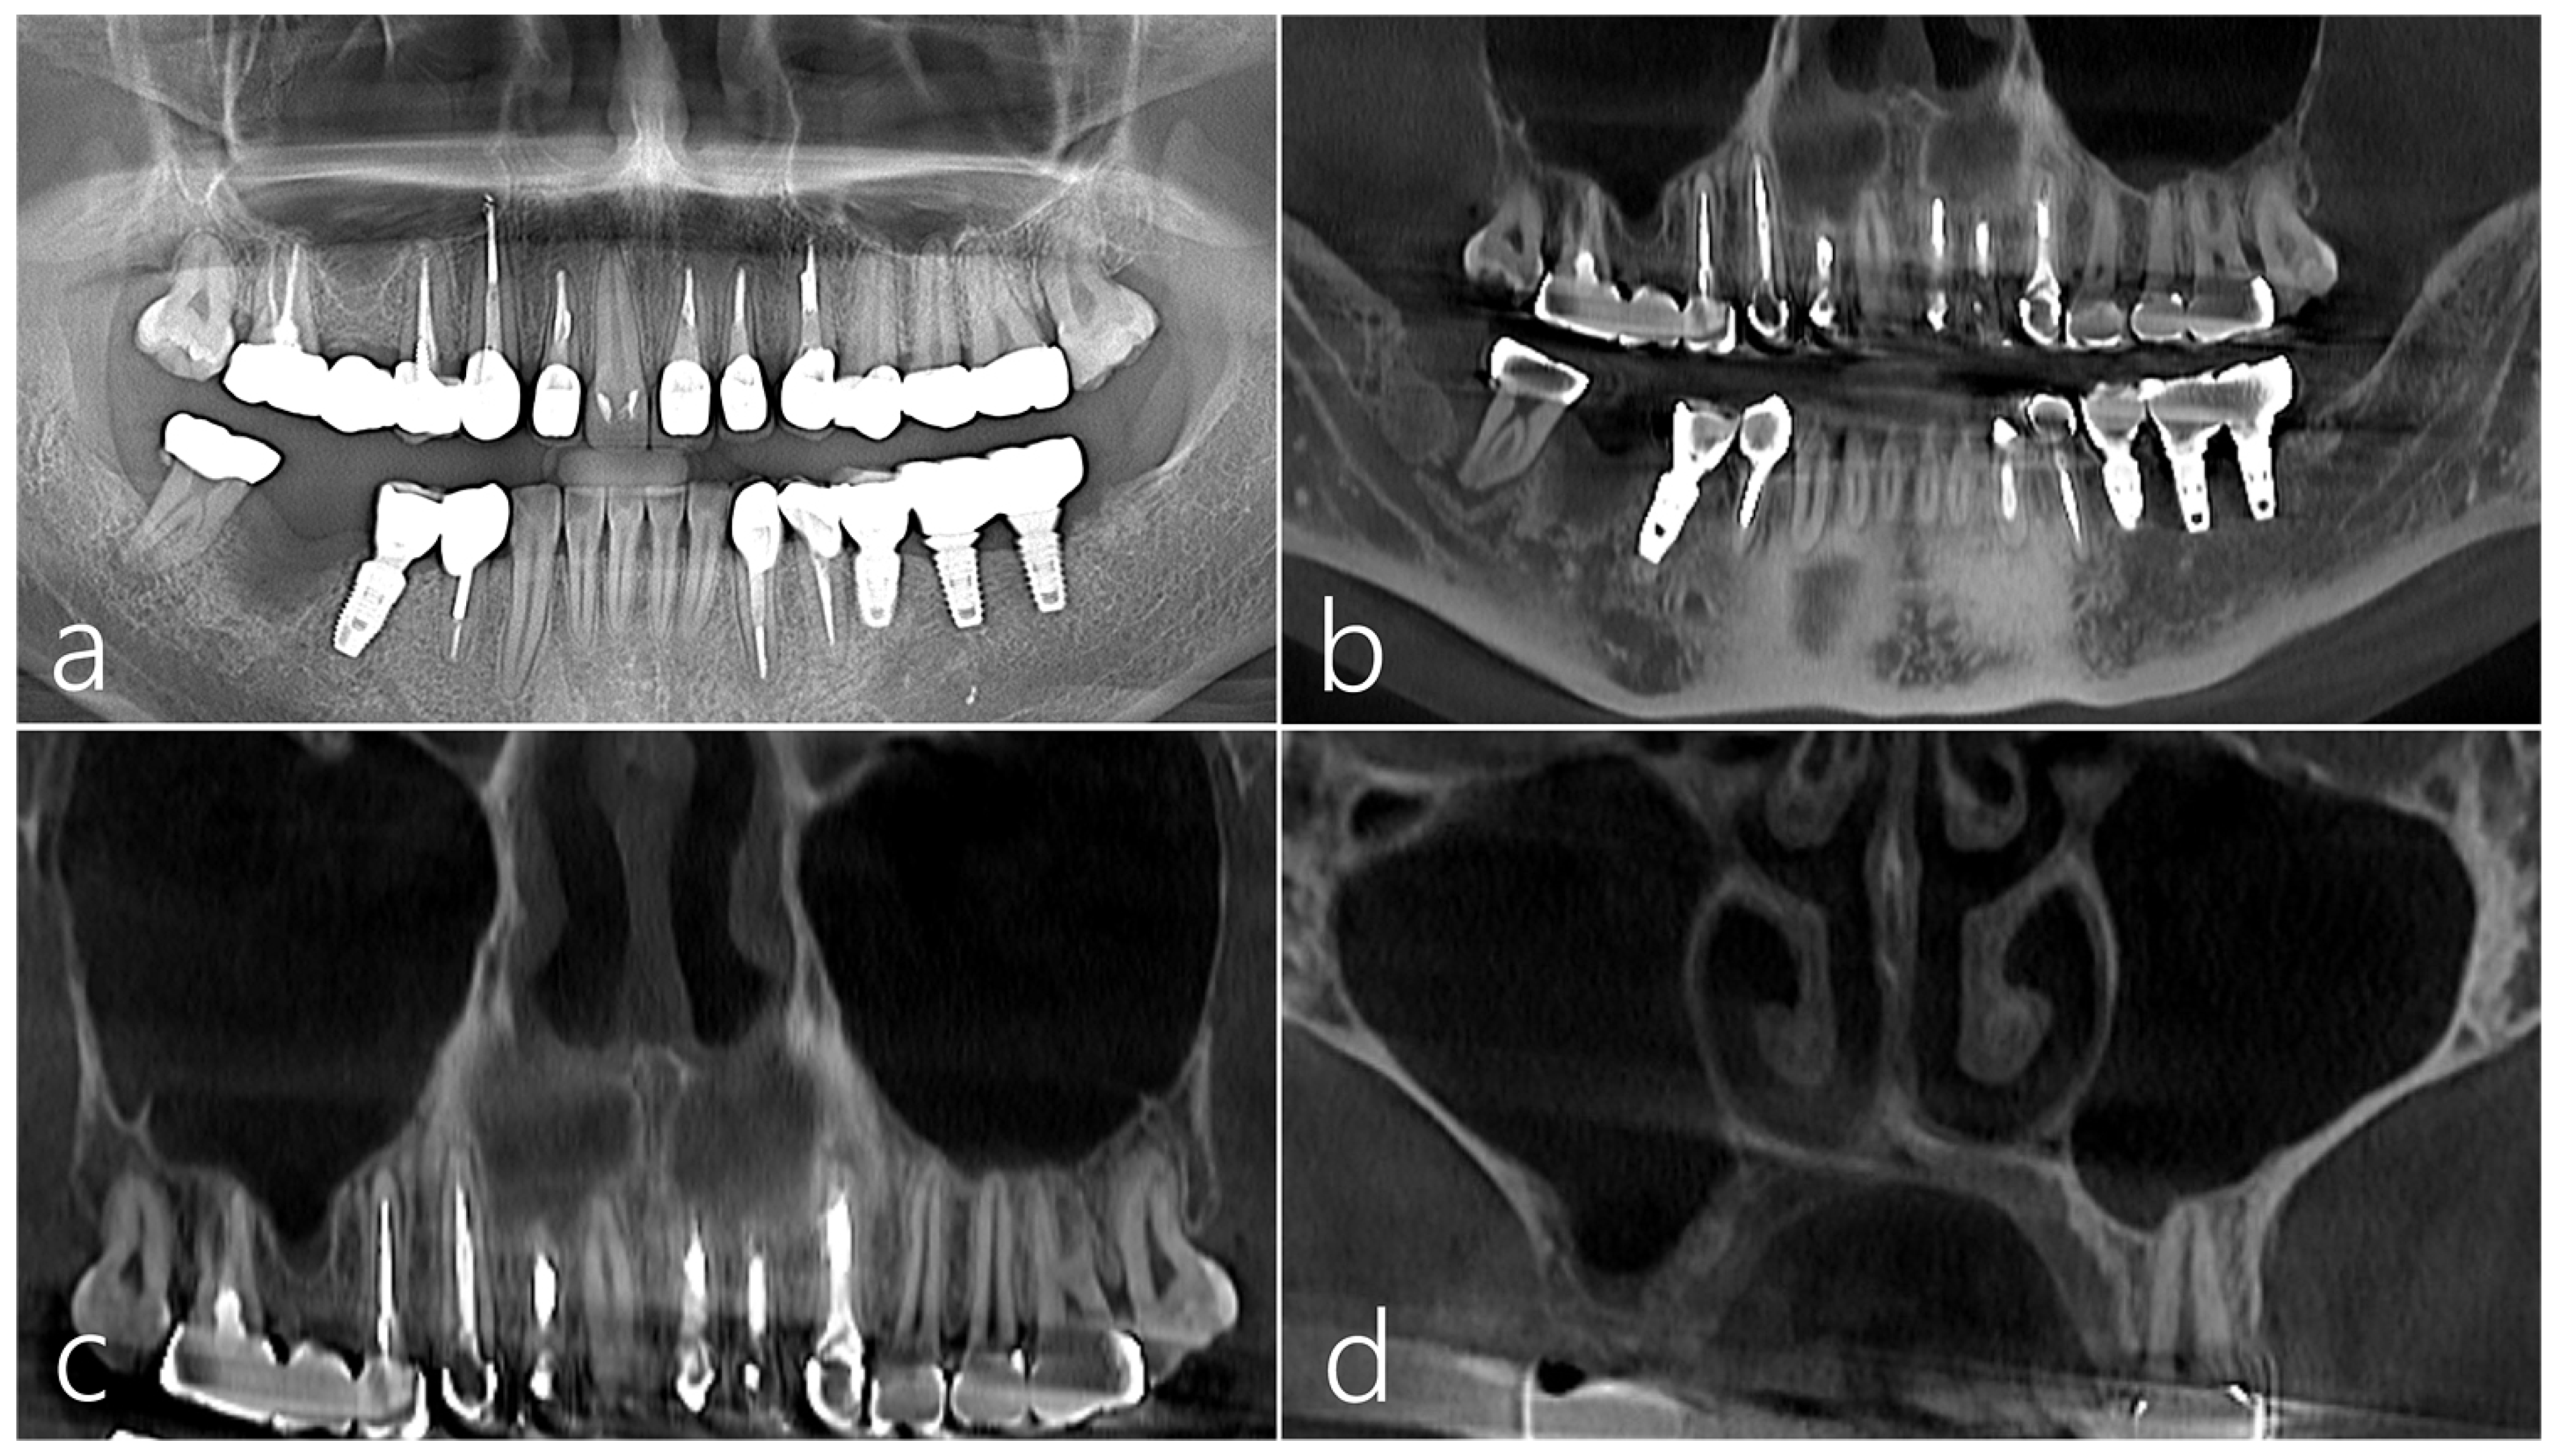

The patient was a 38-year-old female non-smoker without systemic disease. A severe vertical bone defect was observed in the extraction socket of the right mandibular first molar using a panoramic radiograph taken before surgery. Tooth extraction was performed 3 months prior due to periodontal disease (Figure 1a). A vertical ridge deficiency of the extraction socket was observed on a panoramic image of CBCT taken before surgery. A periapical and distal lesion was observed in the #47 tooth. As such, the ascending ramus to the donor site of the autogenous bone was excluded (Figure 1b). On the images of the CBCT taken before surgery, the right maxillary sinus was clear without any existing pathology (Figure 1c), and the lateral sinus wall was maintained at an appropriate thickness. (Figure 1d).

Figure 1.

Case 1 (a) On the panoramic radiography taken before surgery, a severe vertical bone defect was observed in the extraction socket of the mandibular right first molar. Tooth extraction was performed 3 months prior due to periodontal disease; (b) A vertical ridge deficiency of the extraction socket was observed on a panoramic image of CBCT taken before surgery; (c,d) On the panoramic and coronal images of the CBCT taken before surgery, no lesion was observed in the right maxillary sinus, and the lateral sinus wall was maintained at an appropriate thickness. There was no PSAA.

CBCT was taken appropriately for each treatment period. In the sagittal image of the CBCT taken before surgery, the extraction socket of the #46 tooth had a very severe bone defect. A radiolucent image was observed in the distal area of the #47 tooth (Figure 6a). A vertical ridge defect was observed in the cross-sectional image of the CBCT scanned from the extraction socket of the #46 tooth (Figure 6b). Bone bridge and bone graft particles were observed in the sagittal image of CBCT taken immediately after surgery (Figure 6c). Bone bridge and particulate bone graft substitutes were observed in cross-sectional images of CBCT taken immediately after surgery (Figure 6d). In the sagittal and coronal images of CBCT taken 6 months after implant placement, the space between the bone bridge and the lower bone graft substitute was well ossified (Figure 6e,f). The implant was placed 6 months after the bone bridge technique was performed. Uncovering was performed 3 months after implant placement, and the prosthesis was placed 2 months later followed by an immediate post-delivery panoramic radiograph (Figure 6g). In the sagittal and coronal images of CBCT taken 1 year after the prosthesis was delivered, the space between the bone bridge and the lower bone graft substitute was well ossified, and there was no surface bone resorption in the bone bridge (Figure 6h,i). In preoperative CBCT coronal images, a moderately thick lateral wall was maintained, and PSAA was not observed. No mucosal thickening of the maxillary sinus was observed. (Figure 6j). A slight thickening of the sinus mucosa was observed in the CBCT coronal image taken after obtaining the lateral window (Figure 6k). In the CBCT coronal image taken 1 year after prosthesis delivery, the size of the bony window decreased, and no changes were observed in the maxillary sinus (Figure 6l).

Figure 6.

(a) In the panoramic radiography taken before surgery, the extraction socket of #46 tooth had a very severe bone defect; (b,c) A vertical ridge defect was observed in the sagittal and coronal images of the CBCT scanned from the extraction socket of #46 tooth; (d) Panoramic radiography taken after bone bridge procedure; (e,f) Bone bridge and particulate bone graft substitutes were observed in sagittal and coronal images of CBCT taken immediately after surgery; (g) The implant was placed 6 months after the bone bridge technique was performed. Uncovering was performed 3 months after implant placement, and the prosthesis was delivered 2 months later. Panoramic radiography taken after the prosthesis was delivered; (h,i) In the sagittal and coronal images of CBCT taken 1 year after the prosthesis was delivered, the space between the bone bridge and the lower bone graft substitute was well ossified, and there was no surface bone resorption in the bone bridge; (j) Coronal image of CBCT taken at the donor site preoperatively; (k) Coronal image of CBCT taken after the lateral window was removed. Slight thickening of the sinus mucosa was observed; (l) In the CBCT coronal image taken 1 year after prosthetic delivery, the size of the bony window decreased.